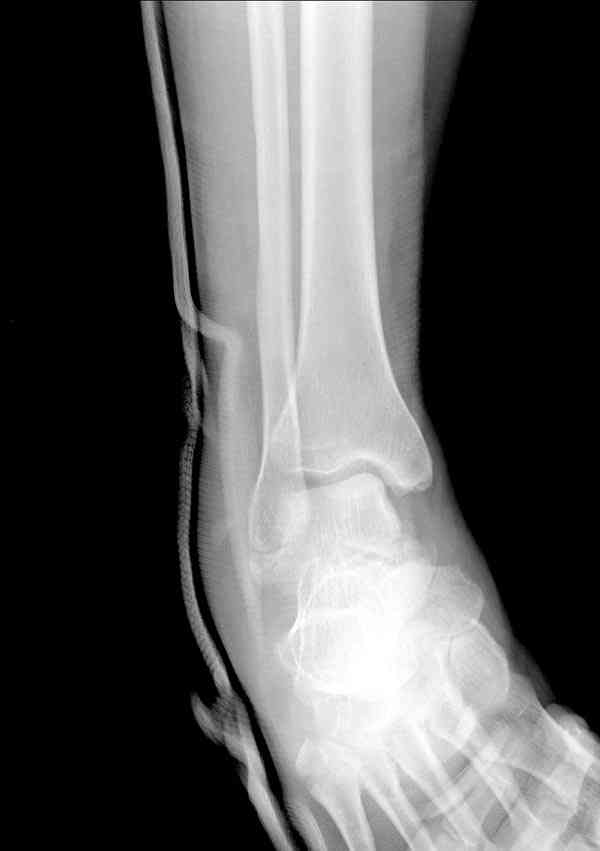

а основании двух видов ренгенограмм невозможно радикально решить о необходимости открытой репозиции или первичного артродеза.

Для оценки состояния нужны дополнительные исследования, например Canale или Broden ренгенограммы и Компьютерная томография.

При переломах тарана всегда имеется риск AVN, а классификация Hawkins поможет разобраться с предполагаемыми осложнениями.

Если в первом типе, когда перелом шейки без смещения, тогда AVN менее 10%, при втором типе когда имеется смещение и вывих тарана в субталарном сочленении меньше 40%, а при типе III когда смещение в голеностопном и субталарном суставах - около 90% и в типе IV, когда происходит полный вывих, риск AVN достигает 100%.

Для оценки состояния нужны дополнительные исследования, например

> Canale или Broden ренгенограммы

повторили рентгенограммы и доделали проекции, к единому мнению все еще не пришли

На ренгенограмме не уловил многоскольчатость тарана, чтобы доказать, конечно, можно было исследовать на КТ, потом КТ дает ориентацию фрагментов.